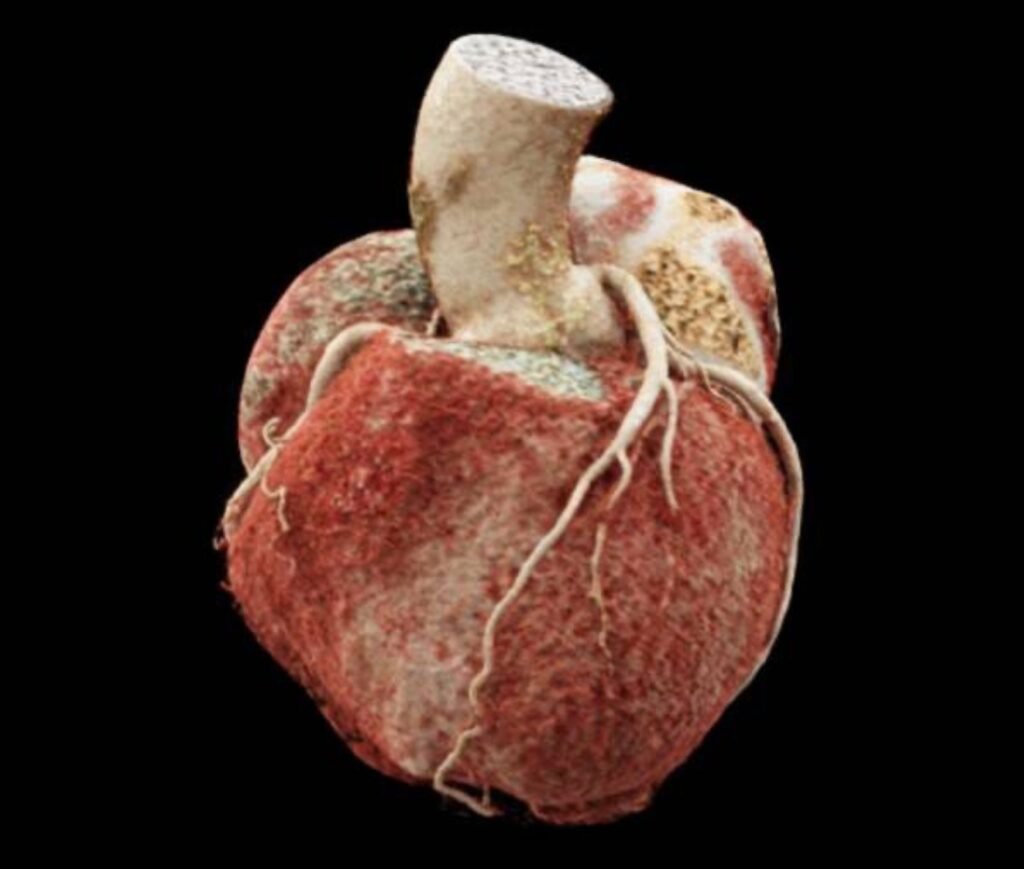

1150 Slice CT Scan machine at Ruby Hall Clinic

1150 Slice CT Scan

A first in India and Asia, this ultra-fast high-resolution CT scanner provides detailed cross-sectional images of the heart and blood vessels. Ideal for cardiac imaging, it captures precise anatomical data with low radiation exposure. Enabling over 100 CT scans in 1 day, giving more patients quicker results and diagnosis with help of advanced technology.